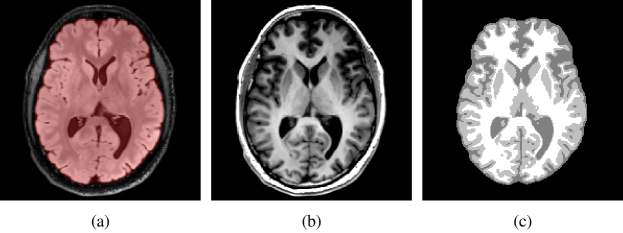

The extracted brain domain was further segmented on the registered T1 BRAVO image into white matter, grey matter, and cerebrospinal fluid using an in-house implementation of the MICO intensity-based clustering algorithm comprising a bias field correction step [33]. Manual corrections were further applied to the mis-segmented basal nuclei and falx cerebri. This last step is crucial to prevent the migration of tumour cells between brain hemispheres via other routes than the corpus callosum, as highlighted previously [8]. The segmentation results were finally merged into a single brain map. An example of T2 FLAIR and T1 BRAVO images with the corresponding brain mask and segmented brain map is depicted in Figure 1.

Refer to caption

Figure 1: Example of processed MR data. (a) Axial slice of the T2 FLAIR image with superimposed segmented brain mask (red). (b) Corresponding slice of the T1 BRAVO image. (c) Segmented brain map obtained with the MICO algorithm followed by manual corrections.